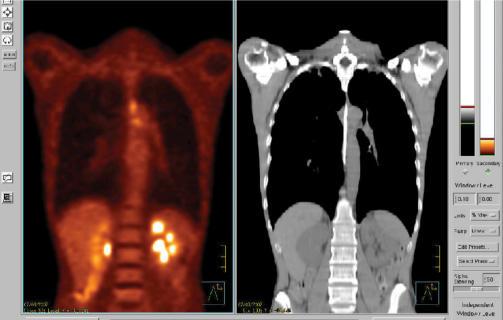

Positron emission tomography (PET)/computed tomography (CT) imaging is frequently requested in Oncology. Radiologists and nuclear medicine physicians are often asked to perform a panel of imaging examinations as part of the initial staging or follow-up of cancer patients. Medical imaging must therefore integrate polyvalent skills enabling imaging specialists to understand and interpret all types of images. In this context, PET imaging combined with non-enhanced CT, and diagnostic quality contrast-enhanced CT scan and optimisation of CT settings, is part of this multidisciplinary approach requiring the specific skills of a radiologist and a nuclear medicine physician. This approach must therefore be conducted in both directions: radiologists and nuclear medicine physicians should both know how to correlate PET and CT images, while preserving the specificities of each discipline. Radiologists need to be aware of several aspects of PET imaging: PET technology, the examination procedure and injection of iodinated contrast agent for high quality diagnostic CT, ideally followed by double interpretation of CT images, PET images and fused images. Radiologists should be familiar with PET imaging, as this procedure may be associated with several pitfalls and artefacts that need interpretation by a trained specialist. The authors analyse the examination technique of PET combined with non-enhanced and/or contrast-enhanced CT and the proposals for optimal interpretation of normal or pathological PET/CT fusion images.

肿瘤学领域经常需要进行正电子发射断层扫描(PET)/计算机断层扫描(CT)成像。放射科医生和核医学医生经常被要求进行一系列成像检查,作为癌症患者初始分期或随访的一部分。因此,医学成像必须整合多种技能,使成像专家能够理解和解读所有类型的图像。在这种情况下,PET成像与非增强CT相结合,以及具有诊断质量的增强CT扫描和CT设置的优化,是这种多学科方法的一部分,需要放射科医生和核医学医生具备特定技能。因此,这种方法必须双向进行:放射科医生和核医学医生都应该知道如何关联PET和CT图像,同时保留各学科的特殊性。放射科医生需要了解PET成像的几个方面:PET技术、检查程序以及为高质量诊断CT注射碘化造影剂,理想情况下随后对CT图像、PET图像和融合图像进行双重解读。放射科医生应该熟悉PET成像,因为这个过程可能会出现一些需要经过培训的专家进行解读的陷阱和伪影。作者分析了PET与非增强和/或增强CT相结合的检查技术,以及对正常或病理PET/CT融合图像进行最佳解读的建议。